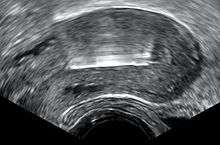

String problems: A small portion of men report that they can feel the strings during intercourse. In this case, strings can be trimmed. However, very short strings can prevent the woman from checking the strings for expulsion.[12] Medical ultrasonography may be required in such cases to check the location of the IUD.